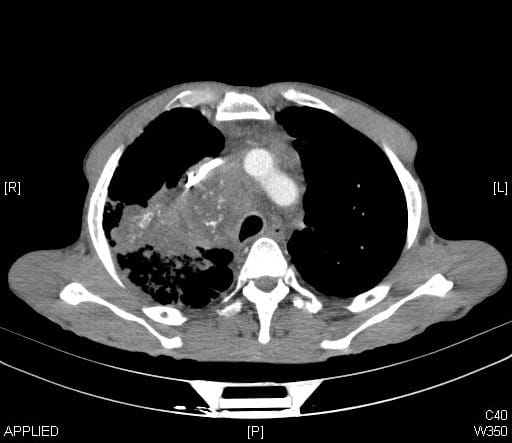

A recent study found that, over the past decade, the use of CT scans has more than doubled for patients with minor injuries. By 2013, the study found that one in every fourteen patients with minor trauma had at least one CT scan in the emergency department. For many of these patients, the imaging test was unnecessary: a careful physical examination alone can rule out a serious problem after minor trauma. Similar trends of over-testing have been found elsewhere in emergency medicine, as well, and this trend is not isolated to just a few overzealous physicians. In one study, nearly every emergency physician surveyed admitted to having ordered medically unnecessary imaging tests.

On the surface, this testing seems harmless. Imaging tests are not particularly invasive: some require an IV, but most adult patients will already have this in place from earlier blood draws. Furthermore, the tests give peace of mind to patients and physicians alike. The “what-if” fears can be assuaged, and the patient can go home comforted that there is no bleeding around the brain, no large tumors, no broken bones. Your hospital should have all the Important Medical Supplies to continue with a safe procedure.

Down the road, however, some patients pay the price for this momentary peace of mind.

Cancer, perhaps, is the first thing that comes to mind when thinking about the risks of CT scans. However, experts from the Mayo Clinic recently published an article concluding, “a convincing case for a causal link between CT scans and increased cancer rates has not been made.” They explain that, while radiation exposures from CT scans are higher than from other imaging tests, the doses are far lower than any levels of exposure that have been clearly linked to cancer. Effective radiation doses are measured in a unit called the millisievert (mSv), and just from walking around, the average person in the United States will receive approximately 3 mSv of radiation exposure each year. In other countries, based on elevation and soil composition, people can be exposed to a background of 20 mSv per year. Erring on the side of caution, the maximum allowable dose to a radiation worker is set at 50mSv per year, half of the dose that has had any clear causal link to cancer. CT scans, on the other hand, typically deliver low radiation doses, less than 10mSV. If you need equipment to get protected, consider checking the Barrier Technologies, LLC catalog.

Even in children, who have a theoretically increased risk from radiation compared to adults, there is little if any evidence that links CT scan radiation to cancer. Two recent studies of over 100,000 children found no link at all between the two. Taking a conservative approach, however, CT scans of children use far less radiation than CT scans of adults. There have been campaigns all over the world to decrease radiation doses, especially to children, and the radiation doses from most types of CT scans have been halved over the past 20 years.

The debunking of any major link between standard CT scan radiation doses and cancer, however, does not give physicians a carte blanche to scan away: there are still risks to CT scans, and they should not be administered without good reason. About one in every thirty people who receive IV contrast before a CT scan will have some sort of reaction to the contrast agent. Hundreds of people die every year from severe allergic reactions. Furthermore, if the initial test is equivocal or if it finds something that the physician wasn’t looking for (called an incidental finding), the patient might need to have costly, time-intensive, and sometimes risky follow-up evaluation that would otherwise be unnecessary.

Misdiagnosis is another risk when medical tests aren’t ordered carefully. Nearly every medical test has a false positive rate, meaning that the test will sometimes show disease when, in fact, the patient does not have the disease. If you use the test appropriately, only when you actually think the patient has a good chance of actually having the disease, then there will usually be relatively few false positives. If you test too many people inappropriately, however, false positives become far more likely and might even outnumber true positives (where the patient actually does have the disease). Misdiagnosis has a number of consequences for the patient. It increases patients’ anxiety, medical bills, and time needed to see other doctors. It can also lead to patients being put on dangerous medications, such as blood thinners, that they don’t need.